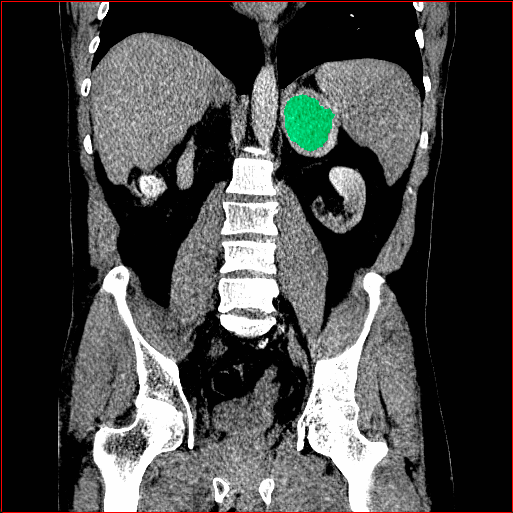

Abdomen Region

1×1×0.71\times 1\times 0.7

mm

512×512×768512\times 512\times 768

Figure 4: MAISI-v2 segmentation-guided results for small to large volume size and three different regions.